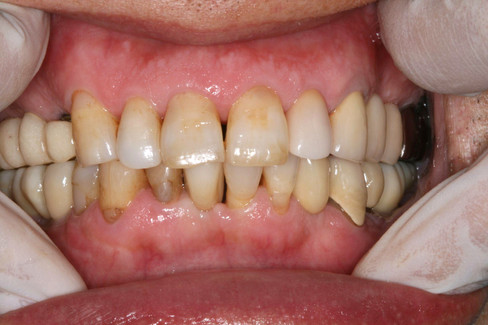

The 1-year follow-up panoramic radiograph and intraoral photograph show good maintenance with no signs of complications

The 3-year follow-up panoramic radiograph and intraoral photograph.

At the 8-year follow-up, clinical and radiographic evaluations revealed well-maintained peri-implant tissues with no signs of marginal bone loss.